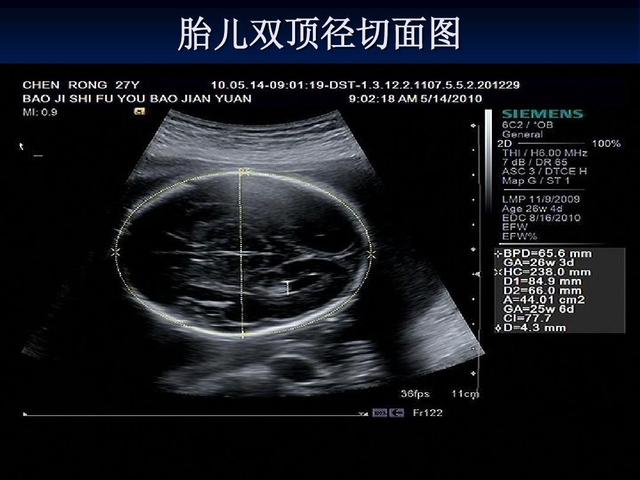

2、预测孕龄、估计胎儿体重。

3、胎儿生长发育的判断;宫内生长迟缓、巨大胎儿。

需用高分辨力实时超声诊断仪。常用线阵或凸阵式探头,频率为3~5MHz。仪器如果备有扇扫式探头(3.5MHz)和阴道探头(5~7.5MHz),则更为理想。经腹壁观察位于宫颈或阴道部位病变或当膀胱充盈欠佳时,采用凸阵式或扇扫式探头(配合腹腔壁适当加压扫查)比较有利。改用阴道超声效果更好。增益调节以正常子宫壁呈低水平回声,膀胱内尿液基本上无回声为准。为观察早孕孕囊内胎心、卵黄囊等细微结构时,宜充分放大图像并调节灵敏度。现代彩色超声诊断仪具有B型超声、M型超声、彩色和频谱多普勒超声等多种功能,配有多种探头,是更为理想的仪器。一方面可做常规产科超声检查,另一方面还可高度灵敏地检测血流变化。后者常用于异常妊娠、异位妊娠和滋养体疾病,胎儿各种心血管疾病,脐带异常,胎盘病变等检查。